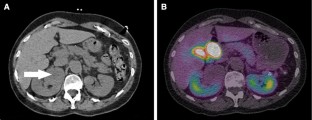

Figure 2